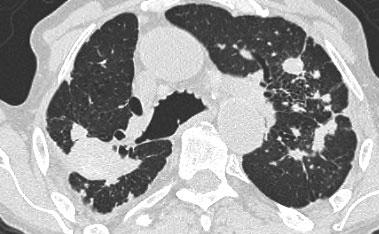

Hình bên trái là một trường hợp bệnh bụi phổi silic cho thấy các nốt có kích thước khác nhau với phân bố ngẫu nhiên và dưới màng phổi.

Một nốt có chứa vôi hóa (mũi tên).

Lưu ý sự vắng mặt của kiểu phân bố theo đường bạch huyết (quanh phế quản-mạch máu và dọc theo các khe liên thùy), vốn là gợi ý của bệnh sarcoidosis.

Cùng bệnh nhân bụi phổi silic như các hình trước, cho thấy một khối tập hợp ở vị trí cạnh rốn phổi thuộc thùy trên phổi phải. Thùy trái cho thấy nhiều nốt có kích thước khác nhau.